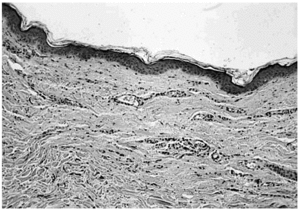

Las tinciones específicas (tricrómico de Masson, tinción para fibras elásticas) revelaron una disminución/ desaparición de las fibras elásticas en la dermis papilar y reticular superficial en ambos casos (fig. 4).

Fig. 4.--Piel afecta (caso 1): desaparición de las fibras elásticas en la dermis papilar y reticular (tinción fibras elásticas ×100).